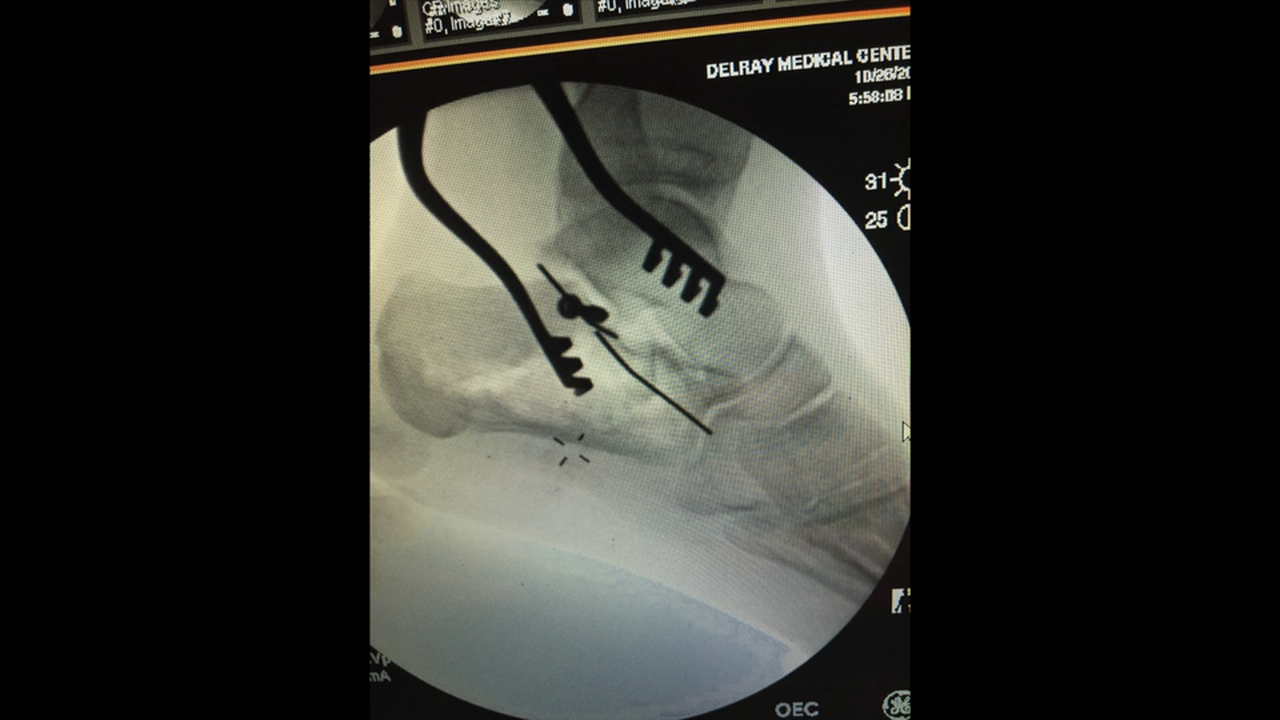

Calcaneus Fracture ORIF

Calc Fx ORIF with ExFix w VO